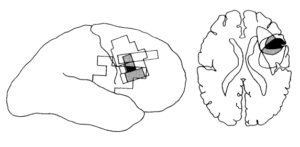

この5名に共通する損傷領域として下前頭回の一部であるブロードマン44野(左半球の言語領域であるブローカ野の右半球相同部位)が共通していること、

また多くの場合その直下の白質繊維にも損傷が見られていたこと、

またこの白質繊維は頭頂葉後部領域と連絡するものであり、

右前頭葉の限局性梗塞後に左側の視力喪失を示す5人の患者が提示される。 病変の位置は、コンピュータ断層撮影法または磁気共鳴画像法を用いて評価した。 病変重複の一般的な領域は小さく、下前頭回の背側面(Brodmannの領域44)とそのすぐ下にある白質に限られていた。 この皮質領域は右半球のBrocaの領域の相同部位の一部であり、人間の運動前野の一部であると考えられている。 この領域に対する損傷の無視との関連は、それが視覚空間における注意を向けるのに重要な役割を果たす可能性があることを示唆している。